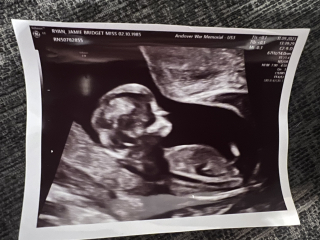

Hi, I am another mum that's had to jump on the nub theory bandwagon. Early Glimpse and Nub Techs have both said boy but The Nub Whisperer has said girl. I will share all images, the last image is of my current pregnancy on top and my son on the bottom just for comparison. I was measuring 12 weeks and 5 days at scan. I have a gender scan in 19 days!!! We can't wait 🥰 please let me know about your experiences with nub theory and what you think of my baby scan ❤️

Nub theory prediction wrong?